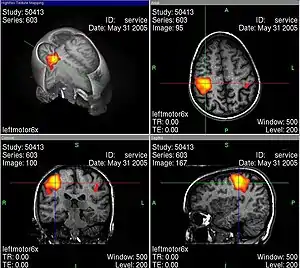

L’usage de l’imagerie cérébrale dans des programmes de recherche en neuropsychologie nécessite de bien maîtriser tous les artefacts et biais statistiques possibles, par exemple lors de l’IRMf en faisant des moyennes spatiales, temporelles et interindividuelles. La base de cet examen est de déterminer des corrélations entre certaines tâches mentales (langage, attention, mémoire…) et des activations spécifiques de zones du cerveau[30].

Les activités électriques du cerveau conduisent à des variations de tension électrique à la surface de la tête, que l'on peut enregistrer avec des appareils convenables. Les neurosciences cognitives actuelles reposent très largement sur le procédé d'imagerie par résonance magnétique fonctionnelle (IRMf). En même temps, ce genre de méthode soulève déjà une série de questions éthiques. Au moyen de l'IRMf, l'activité dans le cerveau peut être mesurée avec une bonne définition spatiale et temporelle. Cette technique conduit à des problèmes éthiques en particulier quand on trouve au moins grossièrement des corrélations entre l'activité neuronale et l'état conscient du sujet. Comment se comporter quand on sait par des méthodes neurologiques, et non par ce qu'elle en dit, qu'une personne pense à quelque chose ou le sent ?

Un exemple classique est le détecteur de mensonge neurotechnologique. Certes, les technologies d'IRMf adaptées en sont encore à l’étude, cependant il existe depuis longtemps des détecteurs de mensonge fonctionnant sur l'EEG. Les Brain Fingerprinting Laboratories ont mis ce genre de technologie sur le marché, et annoncent qu'elles sont utilisées par le FBI, la police américaine et d'autres organisations.

Beaucoup de spécialistes de neuroéthique se voient placés dans un dilemme par ce genre d'applications : d'une part des détecteurs de mensonge pourraient sauver de la prison des innocents, mais d'autre part, il est souvent dit que ce genre de technique lèse l'indépendance de la personne, et pourrait être utilisée abusivement.

En outre, les technologies correspondantes ne sont pas encore complètement sûres. Judy Illes et ses collègues du Neuroethics Imaging Group de l'université Stanford indiquent la force suggestive des images d'IRMf, qui cachent souvent des problèmes réels d'analyse des données[31].

Les images d'IRMf bien connues (voir par exemple ci-contre) sont toujours interprétées selon des modèles qui en permettent la lisibilité. Pendant une tâche cognitive, le cerveau est constamment actif dans un grand volume, et il faut trier pour obtenir des images significatives, dépourvues de toutes les activités apparemment secondaires. Ce genre de tri se fait avec une méthode de soustraction : par exemple si l'on s'intéresse à une tâche cognitive K, alors on mesure l'activité du cerveau dans une situation S1 dans laquelle K est accomplie. Ensuite, on mesure l’activité dans une situation de contrôle S2 qui ressemble à S1, mais qui n'a a priori rien à voir avec la tâche K. Finalement, on soustrait les activités mesurées dans S2 de celles mesurées dans S1, pour voir les activités corrélées avec la tâche K de façon spécifique. Illes souligne qu'il faut toujours garder en tête ces aspects interprétatifs, ce qui peut facilement passer inaperçu devant un tribunal, parce que les juristes n'ont probablement aucune compétence en neurologie.

Turhan Canli explique : « L'image d'un type d'activité basée sur une étude de mauvaise qualité ne peut pas être visuellement distinguée de celle d'une étude exemplaire. On doit être un habile spécialiste pour éventuellement remarquer la différence. C'est là que réside le grand danger d'abus des données d'imagerie auprès d'un public non éduqué, comme le jury d'une cour d'assises. Si l'on regarde les images, on peut facilement oublier qu'elles représentent des déductions statistiques et jamais une vérité absolue[32] ».